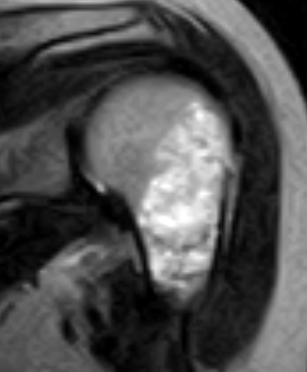

MRI

Large, central enchondroma